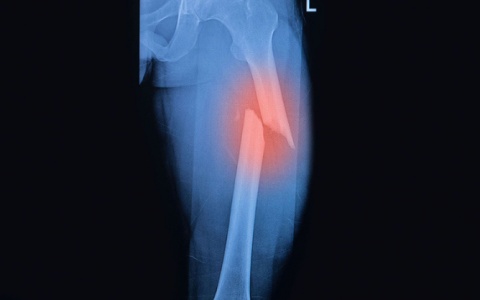

Sau khi thăm khám, chụp X-quang và hội chẩn chuyên môn, các Bác sĩ xác định bệnh nhân bị gãy thân xương đùi trái – Đây là một chấn thương nặng cần được phẫu thuật cố định xương kịp thời để tránh biến chứng. Gia đình bệnh nhân đã tin tưởng lựa chọn Bệnh viện Phúc Hưng là nơi điều trị không phải di chuyển đến các tuyến xa hơn.

Với đội ngũ Bác sĩ Ngoại Chấn Thương giàu kinh nghiệm, ca phẫu thuật đã được tiến hành thành công. Hiện tại, bệnh nhân tỉnh táo, sức khỏe ổn định và đang được theo dõi, chăm sóc tích cực và tập phục hồi chức năng tại khoa Ngoại Chấn Thương.